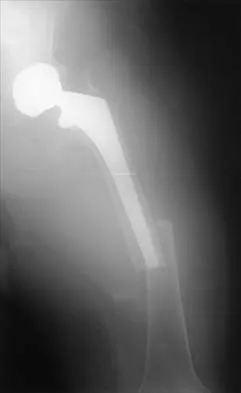

Figure 36a shows the current radiograph of a 65-year-old woman who slipped and fell. History reveals that prior to the fall she was actively functioning without pain. Figure 36b shows a radiograph obtained 1 year ago. Based on the fracture pattern, the failure is most likely related to

Detailed Explanation

The radiograph shows a fracture distal to the prosthesis in a stable, apparently well-fixed prosthetic stem. The well-fixed prosthesis-bone composite is stiff, creating a modulus mismatch between the proximal and distal femur. Therefore, the risk of fracture, particularly in osteoporotic bone, is increased at this level. Revision of the stem to a longer construct is unnecessary, and standard plate and screw fixation has been shown to yield union rates of greater than 90%. Nonsurgical treatment of fractures distal to the tip of the prosthesis results in high nonunion rates, reported to be from 25% to 42%. Johansson JE, McBroom R, Barrington TW, Hunter GA: Fracture of the ipsilateral femur in patients with total hip replacement. J Bone Joint Surg Am 1981;63:1435-1442. Bethea JS III, DeAndrade JR, Fleming LL, Lindenbaum SD, Welch RB: Proximal femoral fractures following total hip arthroplasty. Clin Orthop 1982;170:95-106.